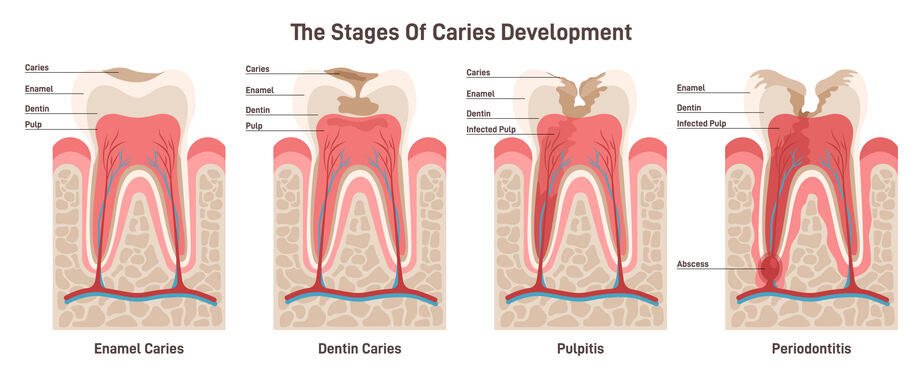

2. Stages of Caries Progression:

Dental caries develops gradually, often before noticeable symptoms arise. The progression unfolds through the following stages:

Incipient Caries (Demineralization):

- Bacterial acids initiate the process by dissolving enamel minerals, resulting in localized subsurface demineralization, clinically visible as opaque white spots.

- Treatment at this stage often re-mineralization with fluoride.

Enamel Caries (Enamel Breakdown):

- Continued acid exposure weakens the enamel, leading to the formation of microcavities – the initial structural defects. Typically, this stage is asymptomatic.

- Treatment at this stage often involves a dental filling.

Dentin Caries (Dentin Involvement):

- If left untreated, the caries progresses to the dentin, a softer tissue more susceptible to bacterial degradation. The dentinal tubules contribute to increased sensitivity and accelerated decay. Patients may begin to experience heightened tooth sensitivity to hot, cold, or sweet stimuli.

- Treatment at this stage often involves a dental filling.

Pulpitis (Pulpal Involvement):

- Bacterial invasion compromises the dental pulp, causing inflammation, pain, and potential necrosis. Patients at this stage often experience severe pain, which may be unresponsive to over-the-counter pain medication and disrupt sleep. While sometimes ice can provide temporary relief, immediate dental intervention is crucial.

- Treatment at this stage often involves root canal therapy.

Periodontitis (Periapical Abscess):

- The infection can spread to the periapical tissues, leading to abscess formation, requiring advanced endodontic treatment or extraction. At this point, the inflammation has extended beyond the root and into the surrounding bone, significantly complicating tooth preservation.

- While root canal therapy is still necessary at this stage, the long-term prognosis is generally less favorable compared to earlier interventions. At Boston Finesse Dentistry & Implant Center , however, we remain dedicated to thoroughly exploring all available options to preserve your natural tooth.